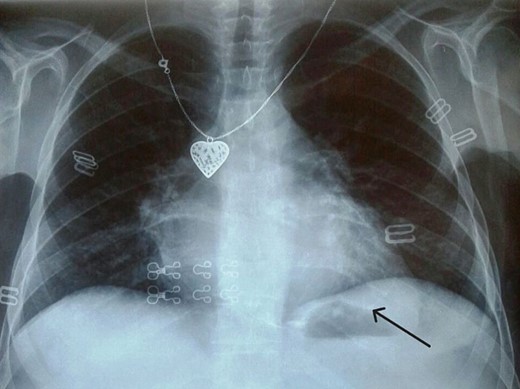

Electrocardiogram (Fig. 1) showed an atrial fibrillation at 120 c/mn with normal axis and a T wave inversion in anterior. Chest radiography (Fig. 2) revealed pericardial calcifications and a mild cardiomegaly. Transthoracic echocardiography (Figs 3–5) showed a pericardial thickening, an important distension of left atrium (LA diameter = 66 mm, LA surface = 33 cm2) and the inferior vena cava (23.7 mm), a calcified mitral leaflets as well as the subvalvular apparatus, restriction of the posterior mitral leaflet with moderate mitral regurgitation (Pisa: 6 mm and ERO: 35 cm2), dilated right heart cavities with moderate tricuspid regurgitation and severe pulmonary hypertension (62 mmHg), preserved left ventricular systolic function (EF LV: 63%) with paradoxical septum. The patient was on lasilix 40 mg one tablet per day, aldactone 50 mg one tablet per day and digoxin 0.25 mg one tablet per day.

Chest X ray showed pericardial calcification around heart (arrow).